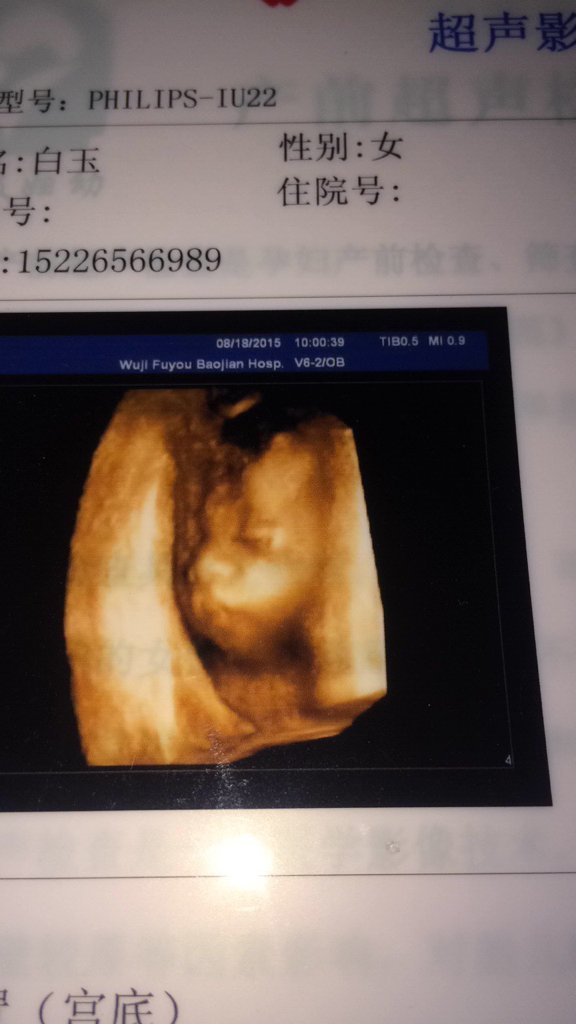

我四个半月做三维排畸和25周做四维彩超都是显示结果正常,没有兔唇 但是我看四维彩超给宝宝照的头部嘴 我四个半月做三维排畸和25周做四维彩超都是显示结果正常,没有兔唇。但是我看四维彩超给宝宝照的头部嘴唇好像兔唇,我好担心宝宝会得兔唇啊,普通B超能照出兔唇来吗? 点击展开 匿名用户 2015-08-21 20:06 为您推荐: 其他回答 退一万步讲。就算真的是,现在的美容业对于兔唇完全不值一提 匿名用户 2015-08-21 20:20 不用担心 如果是兔唇医生会告诉你的 医生要是没说就不是的 接梦槐_prTU 2015-08-21 20:08 为啥不问问医生呢? 匿名用户 2015-08-21 20:07 相关问题 孕32周以前没做过三维彩超,怎么才能检查到胎儿有没有兔唇? 怀孕七周生气了,宝宝会有兔唇么? 看到爱心提示说怀孕6周情绪过于激动暴躁会生兔唇宝宝,,好可怕,最近几天我有上火过,这该怎么办呢?好